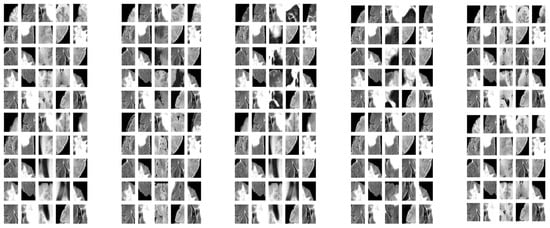

The results demonstrate that the proposed patch-based CNN can accurately segment brain tumors in MRI scans. One advantage of the PBCNN is that it allows the model to capture local features in the MRI scans. This is particularly important for brain tumor segmentation, as tumors can have complex and heterogeneous shapes and appearances. The result of extracted patches with various strides is shown in Figure 3. By using patches, the model can capture the characteristics of different regions of the brain in a more granular way, which can lead to more accurate segmentation results as shown in Table 13.

Figure 3.

Sample of Extracted Patches.